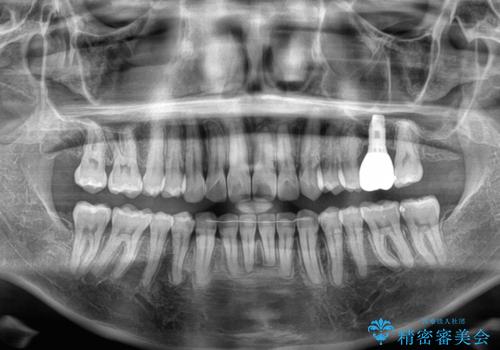

インビザラインによる矯正治療と奥歯のインプラント治療

- 全体的なデコボコと、以前抜歯した歯のスペースを閉じた部分が気になるとのことで来院された患者様です。

左上第一大臼歯を抜歯した際に、スペースを閉じたそうですが、歯が傾斜してものが挟まって不快とのことでした。

インビザライン矯正で全体の歯列と整えるとともに、左上第一大臼歯部にはスペースを作り、インプラントによる補綴治療を行うこととしました。

歯の傾斜が改善され、インプラントによるクラウンが装着されたことで、物が挟まることもなくなりました。